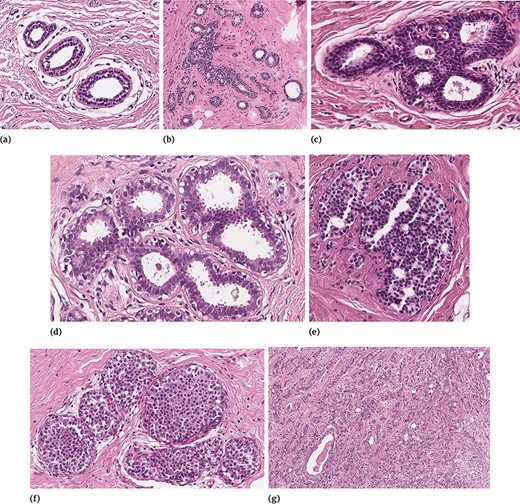

In order to clarify the description of the different tissue subtypes, a brief description of the mammary gland should be considered. The breast is a modified apocrine sweat gland, made up of 15–25 independent glandular units called lobes, each of which is formed by a compound tubulo-acinar gland. The lobes are composed of adipose tissue and divided by connective tissue septa. Inside each lobe, the main ducts branch into terminal ducts, each of which leads to a lobule that is made up of many berries to form the ductulo-lobular terminal unit. Detailed information on lesions included in BRACS can be found in (24). The specific features of the different sample tissue subtypes are briefly summarized in the following, and a representative example for each of them is shown in Figure 3.

Examples of different tissue samples: (a) N, (b) PB, (c) UDH, (d) FEA, (e) ADH, (f) DCIS and (g) IC.

Normal Tissue

In normal mammary glandular tissue, there are two types of epithelial cells (the luminal layer and the basal myoepithelial layer) and two types of stromal cells (interlobular stroma and intralobular stroma). Differently from PB, the ratio between epithelial component and stroma is preserved.

Pathological Benign

Benign breast lesions can be grouped according to the risk of developing invasive carcinoma and include several groups of histological entities classified in relation to morphology. In our study, because of differential diagnosis, in the PB category we included both non-proliferative lesions and proliferative lesions with the exception of UDH, FEA and ADH, which were considered as three independent subtypes. Therefore, PB includes cyst, apocrine metaplasia, ductal ectasia, squamous metaplasia, atrophy, stromal fibrosis, mastitis, sclerosing adenosis, papilloma, radial scar and simple and complex fibroadenoma.

Usual Ductal Hyperplasia

UDH has a rate of occurrence of 20% (25) and is characterized by an increase in the epithelial layers. It is a cohesive proliferation of disorderly distributed but oriented cells. It can have different architectural aspects (solid pattern, fenestrated pattern and micropapillary pattern). Even if UDH shares some architectural features with ADH and DCIS, it does not show atypia.

Flat Epithelial Atypia

FEA represents the 3.8–10% of core needle biopsy samples (25) and is a proliferative lesion characterized by low-grade cytological atypia, cell monomorphism, loss of polarity and orientation with respect to the basement membrane, presence of apical snout, endoluminal secretion and frequent calcifications.

Atypical Ductal Hyperplasia

ADH is a proliferation of monomorphic cells, which only partially fill the ductal spaces. Architectural aspects include a solid pattern, a cribriform pattern and a papillary pattern. The cytologic atypia is similar to that of low-grade DCIS, but the lesion spans no more than 2 mm or has an insufficient architectural atypia involving only partially ducts and/or lobules. Studies suggest that 5–20% of core needle biopsies are ADH and 10–20% of them generally upgrade to DCIS or IC (25).

Ductal Carcinoma in Situ

In situ carcinoma is a malignant proliferation of epithelial cells that fills the entire duct, without evidence of stroma invasion. Typically it involves multiple adjacent ductal spaces. It can have cribriform, solid, papillary and micropapillary patterns.

Invasive Carcinoma

IC is characterized by the invasion of tumor cells infiltrating the breast stroma with loss of peripheral myoepithelial cells. The presence of the myoepithelial cell layer is an important distinction of DCIS from IC.

Detecting certain subtypes is particularly challenging as some morphological patterns can be shared by several classes. For instance, ADH shares morphological similarities with DCIS. In certain cases, it even includes all the features of DCIS, but is simply limited in size. Also, UDH, ADH and DCIS are all characterized by an intraductal growth pattern, which makes these classes difficult to classify and differentiate in H&E-stained sections.